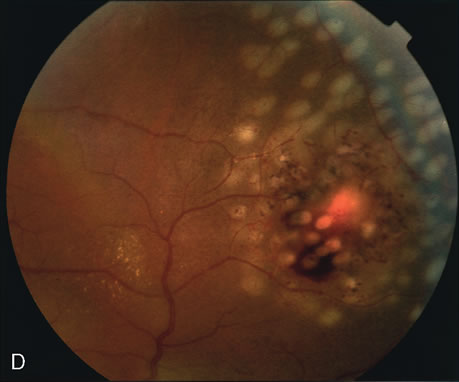

PCV is characterized by the presence of dilated, choroidal vascular channels ending in orange bulging polyp-like dilations in the peripapillary and macular area. Associated features are recurrent subretinal hemorrhage and vitreous hemorrhage, relatively minimal fibrous scarring, absence of retinal vascular disease, pathologic myopia, and signs of intraocular inflammation. FA demonstrates the presence of the dilated vascular channel (Fig. 14 and 15). However, the presence of blood and exudation may block the details of the choroidal circulation on the angiogram. In these cases, ICG angiography can better demonstrate the presence of a distinct network of vessels within the choroid because the larger choroidal vessels are filled with dye.

Fig. 14. A. Color photograph of the right eye shows a ramified pattern of choroidal vascular abnormality irradiating from the peripapillary area toward the macula. The dilated vascular channels end with bulging polyp-like structures. A larger, orange, saccular dilation is seen inferior to the macula (white arrow); leakage of fluid from this vascular abnormality results in serosanguineous pigment epithelium detachment (black arrows). B. The corresponding fluorescein angiogram composite highlights the vascular lesion in the peripapillary area and the serosanguineous detachment of the pigment epithelium that extends inferiorly and temporally off the macula.